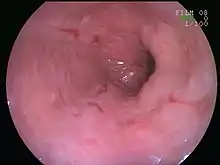

| An esophageal ulcer visualized by esophagoscopy: the reddened area at 10 o'clock on the surface of the mucosa. | |

Esophagitis can be diagnosed by upper endoscopy, biopsy, upper GI series (or barium swallow), and laboratory tests.[4]

An upper endoscopy is a procedure to look at the esophagus by using an endoscope. While looking at the esophagus, the doctor is able to take a small biopsy. The biopsy can be used to confirm inflammation of the esophagus.